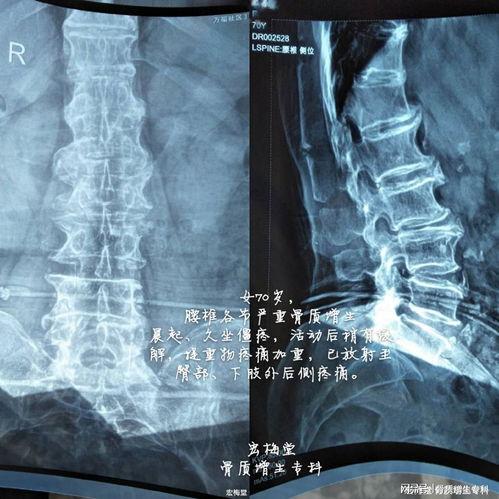

首先,咱们得先弄明白什么是腰椎骨质增生。简单来说,就是腰椎部位的骨头边缘长出了多余的骨刺,这会让你的腰部感到疼痛,甚至影响到日常活动。不过别担心,通过适当的锻炼,可以缓解症状,改善生活质量。